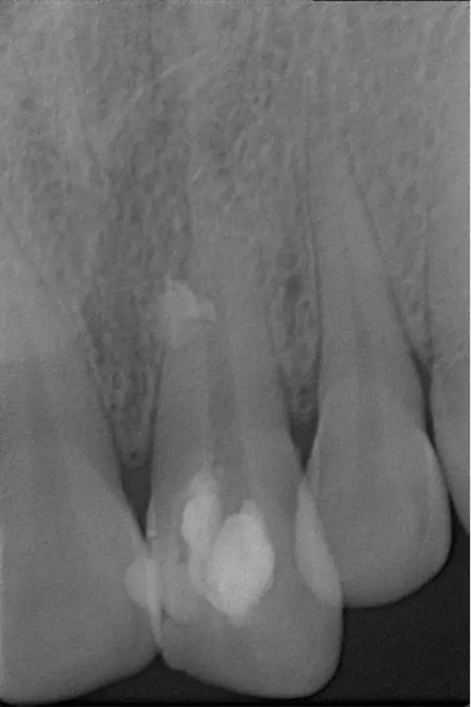

術(shù)后片

隨訪半年后,癥狀消除,熱牙膠根充